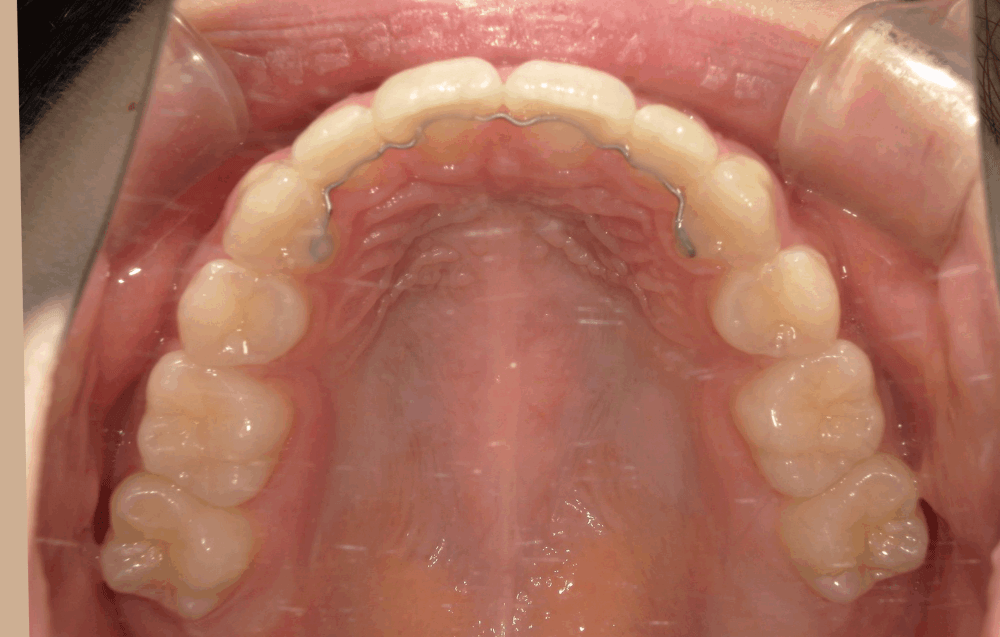

治療後の写真では、歯並びのガタつきが整い、前歯の角度も自然に改善されています。

Eラインに対してもバランスが取れ、力を入れなくても唇を閉じられる、リラックスした口元になりました。

治療後(15か月)

叢生、上顎前突を解消。正中線のずれも改善し、噛み合わせが良くなりました。 ※治療結果は患者様によって個人差があります。 |

| その他治療に関する情報 | 前から5番目の歯を左右計2本抜歯、ゴムかけを頑張って頂いたので、治療期間を短縮できた可能性があります。 |